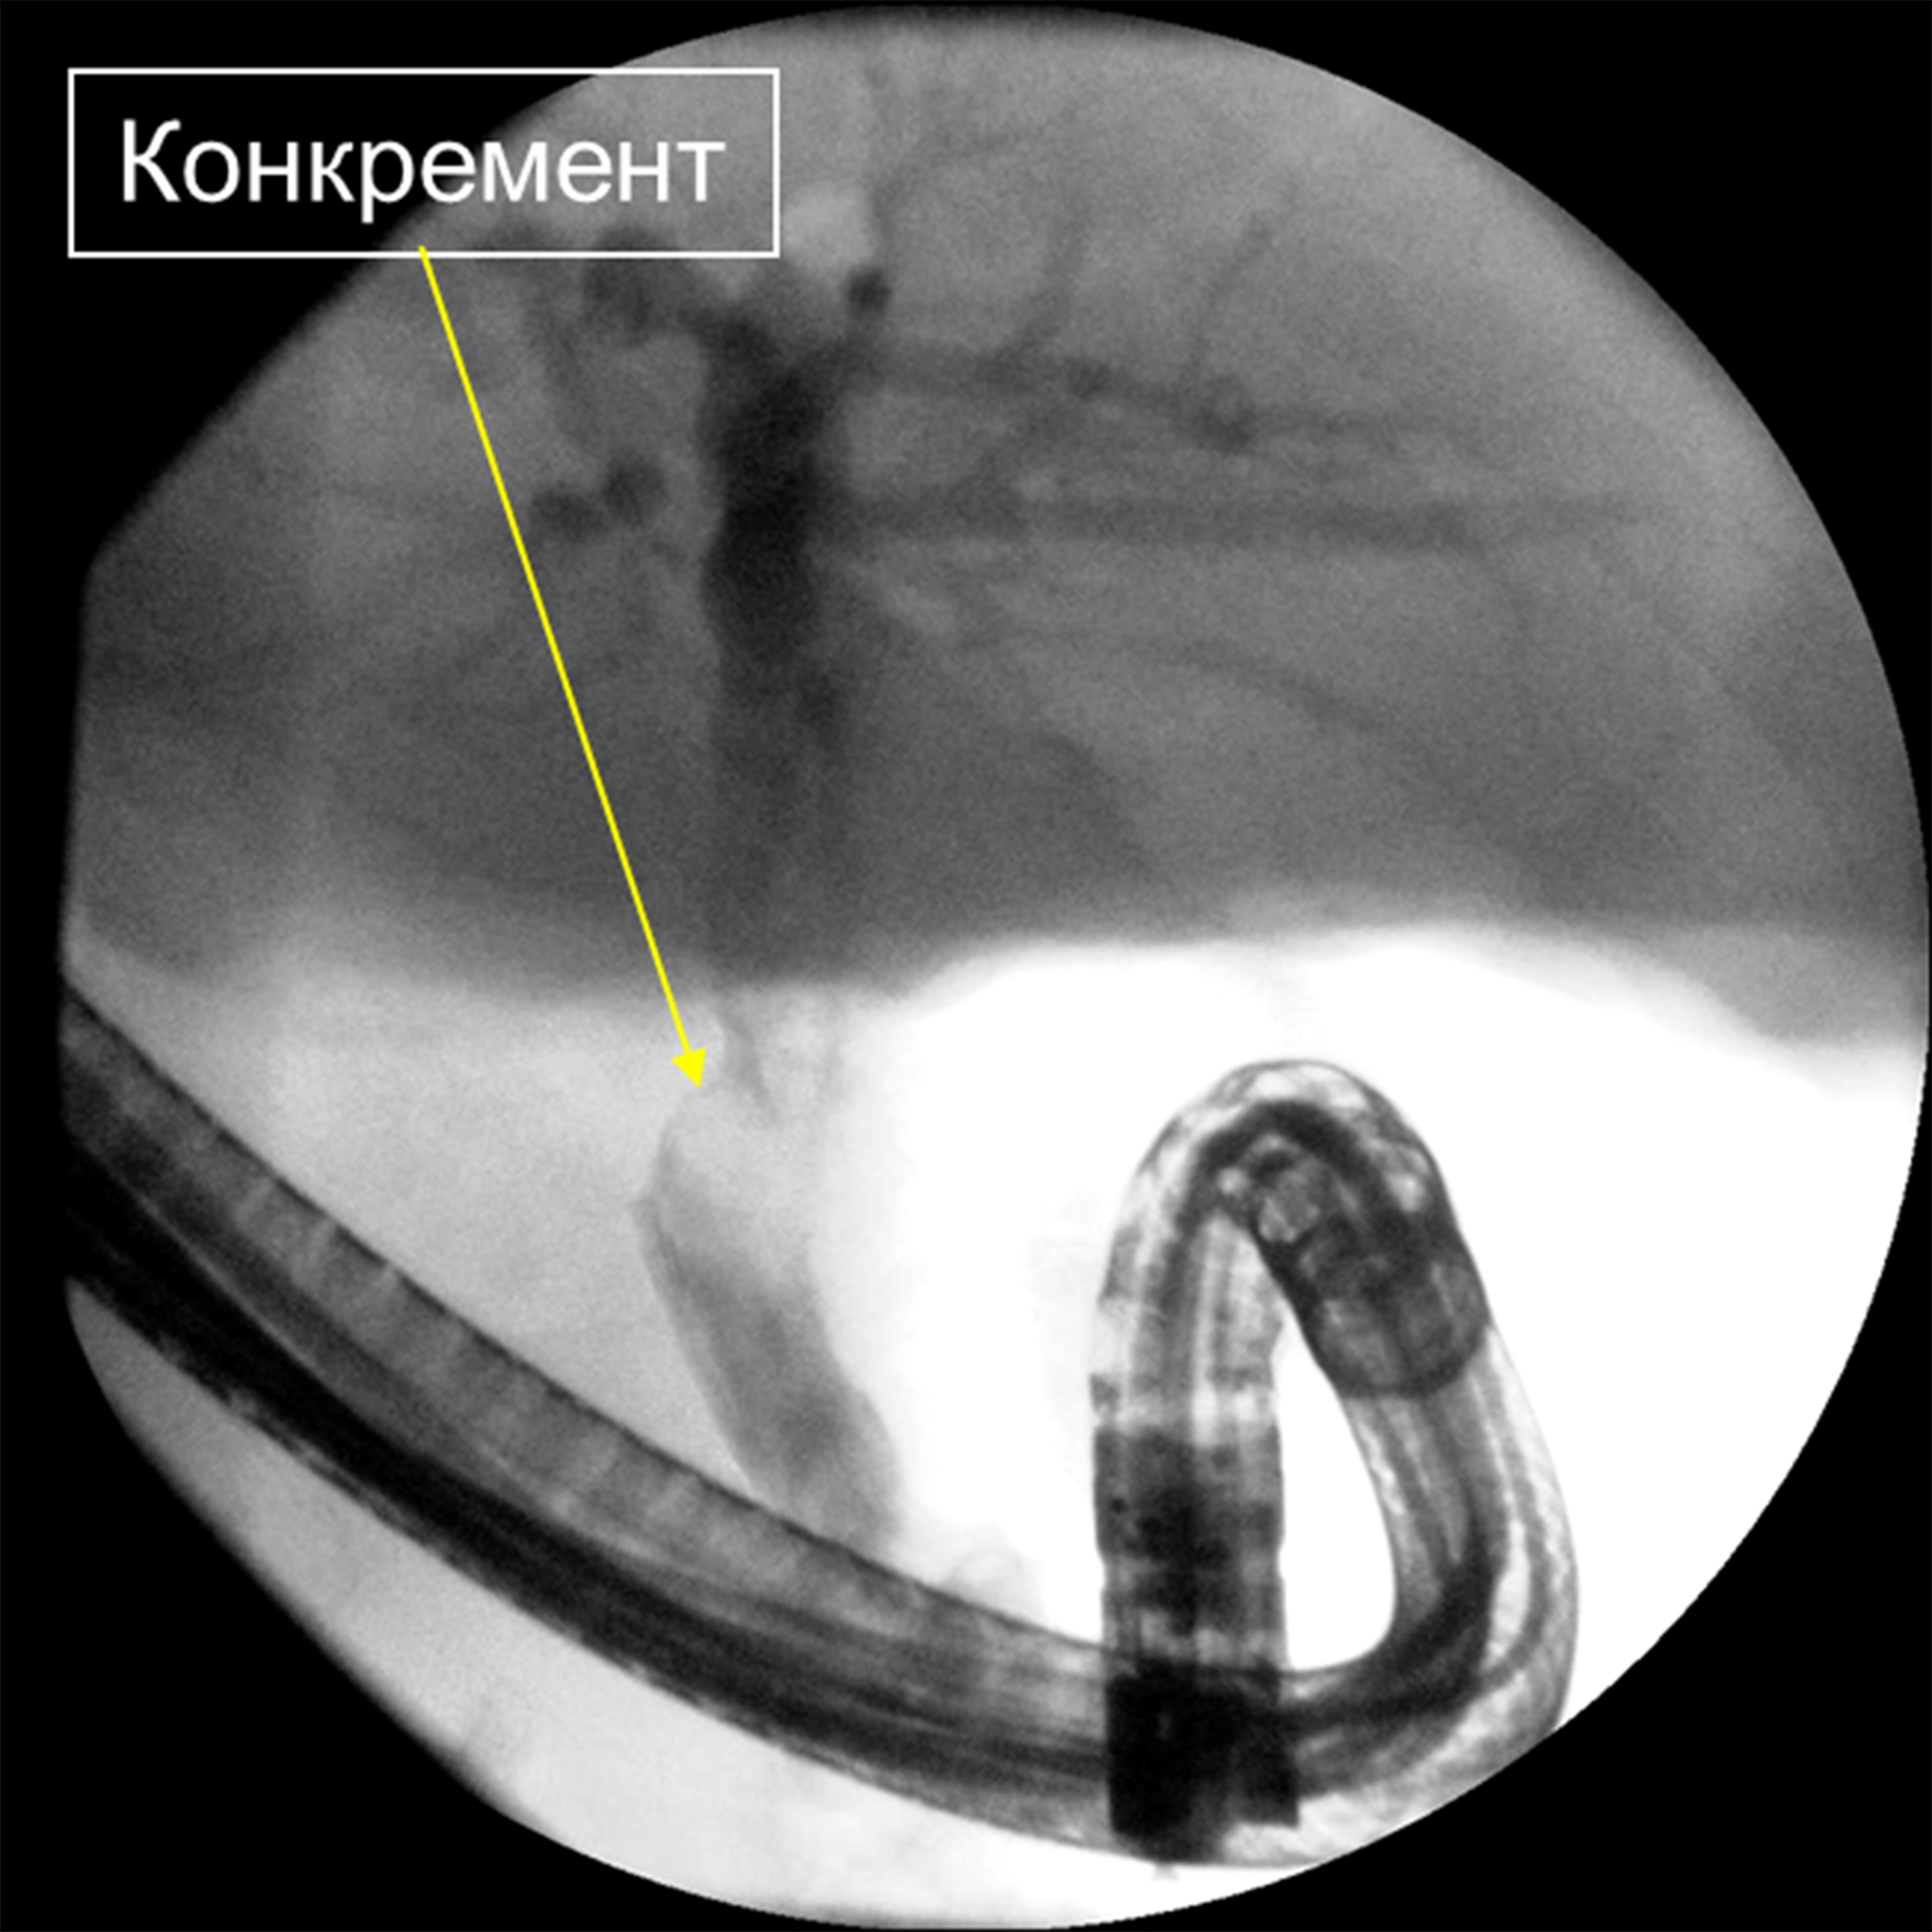

Представлено клиническое наблюдение пациента с желчнокаменной болезнью и так называемым трудным холедохолитиазом. Ввиду развившихся осложнений – механической желтухи и гнойного холангита, а также вследствие большого операционного риска от открытого оперативного вмешательства решено воздержаться. Попытки эндоскопической литэкстракции традиционными способами не увенчались успехом. Выполнены контактная электроимпульсная литотрипсия, литэкстракция. Это позволило устранить холедохолитиаз, восстановить проходимость желчных протоков, ликвидировать холангит и обеспечить возможность безопасного планового оперативного вмешательства по поводу хронического калькулезного холецистита.

Эндоскопическая ретроградная контактная электроимпульсная литотрипсия и литэкстракция